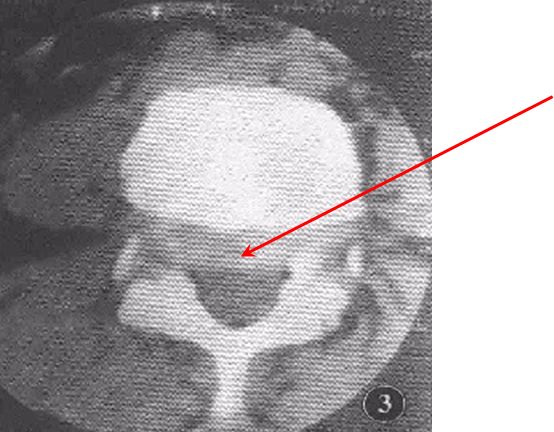

CT扫描

椎弓根下层面可见2~9cm锯齿样裂隙,宽窄不一,走行不定,扫描倾斜时与椎间盘层面正常光滑关节面呈双关节面。

椎管前后径延长,可呈“双管征”。

滑脱椎体“双边征”

椎间盘于相邻椎体层面以相反方向超出椎体边缘“夹心征”。